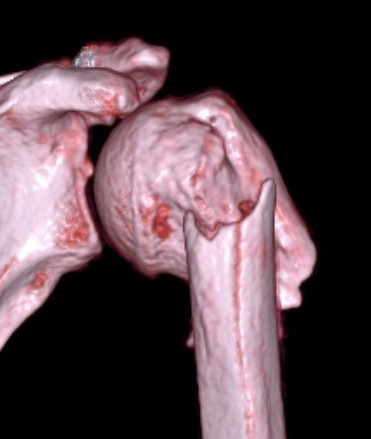

Four part

Avascular necrosis (AVN)

In most fractures, arcuate artery is disrupted, but head survives

- posterior circumflex artery is sufficient

- risk increases with amount of displacement

- 4 part fracture 30%

- 3 part fracture 15%